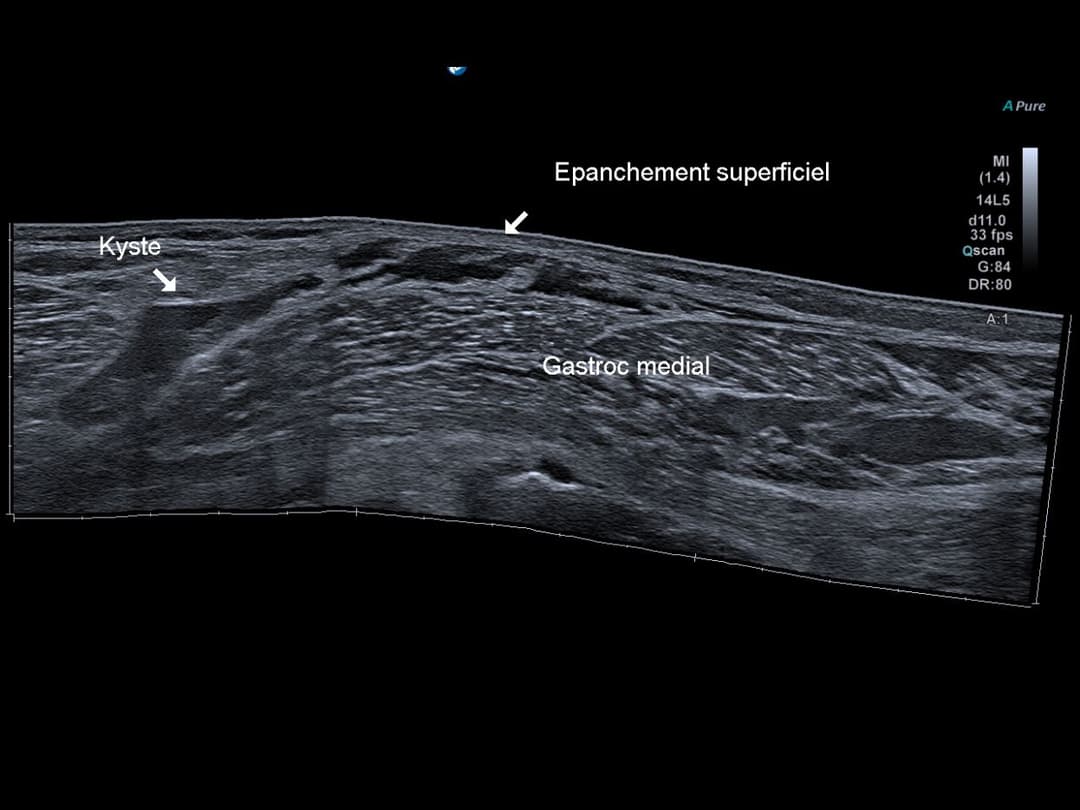

Échographie

Vu panoramique de la zonne pathologique, épanchement liquidien provenant du contenu du kyste qui se développe dans les parties molles superficielles en regard du muscle gastrocnémien médial.

Perte de tension du pôle inférieur du kyste traduisant sa fissuration